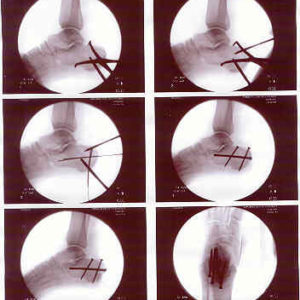

Do you think these might be ‘Piffin’ screws?

My son Matt broke his calcaneus (heel bone) in a fall while rock climbing a week ago, and had surgery yesterday to screw the pieces back together. He will be on crutches for at least 6 weeks.

Sorry about the misleading title, I am trying to keep my sense of humor about this.

Well, the resolution on those X-rays is pretty poor, but most likely those are one "cancellous" screw and two "cortical" screws. Cancellous screws are designed for purchase in cancellous bone, which is the porous bone tissue on the inside of bones. "Cortical" bone is the dense shell on the outside of the bone. Like Piffin screws (which, if I understand correctly, are just drywall screws), cancellous screws have a smaller core diameter and a larger thread diameter and pitch to try to get a better grip without pulverizing the material they pass through. Cortical screws have a thicker, stronger core and a tighter thread pitch.

Modern bone screws may be made of surgical stainless steel (most common) or titanium (more expensive, modulus of elasticity is closer to that of bone).

They can be fully threaded or partially threaded for use as lag screws; self-tapping or may require the hole to be tapped (virtually all bone screws are pre-drilled); and can be solid or cannulated, so that they can be placed over a thin guide wire that is inserted under fluoroscopic (live X-ray movie) control to minimize damage while the surgeon finds exactly the right place to put it. The intra-operative X-rays show two such guide pins, as well as a couple of "joy stick" pins that are used to manipulate the fragments into position.

There are even special screws that have different pitches, wider near the tip and narrower near the head, so that two pieces of cancellous bone can be joined with compression (lag screws only work if one of the pieces has a good hard cortex on it).

Sorry to hear about your son. From here it looks like they got a good reduction. :)

Ah, the first three had me confused. They're apparently during the surgery, and you can see forcepts in the first two.

The screws DO look a lot like Piffin screws. Maybe Piffin gets a royalty everytime someone breaks something? (I'm guessing they're stainless-steel and would look a lot like trim screws.)